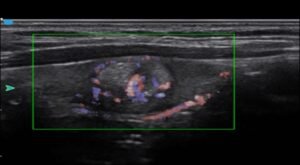

VS Flow

SIUI VS Flow to technologia obrazowania przepływu Dopplera o wysokiej rozdzielczości

przestrzennej. Zbieranych jest o 30% więcej sygnałów bocznych w celu zwiększenia czułości

całego przepływu, zwłaszcza przepływu o małej prędkości.